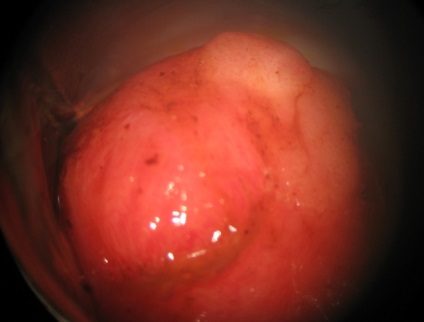

Query „nyaki cysta, hogy ez egy fotó” - az egyik legnépszerűbb az interneten. Mi választ, hogy a nyaki ciszta - különféle rendellenes test és a buborékok elhelyezkedik testszövetekben a bejáratnál a méh. Az oka ennek a típusú tumorok nevezett gyulladás vagy bakteriális fertőzés.

Kép külleme ciszták a méhnyak, azt mutatja, kóros előre. Ilyen nagy genny képződése befolyásolja legtöbb nyálkahártyák és okozhat betegséget és a kísérő betegségek.

nyaki ciszta - a fenti képen látható - lehet csatolni váladékot a helyén a sérülés és gennyes gócok.

méh ciszta - a fenti képen látható - lehet kifejezni formájában nagy gyulladt gennyes képződmények, amelyek gyakran jelennek meg szerte a vérerek és a kötőszövet.

A fenti fotó ciszták a méhnyak azt mutatja, hogy a folyamat a daganat növekedését gyulladást okoznak az erek a kapcsolódási hely a szövetekben.

A fotó, úgy néz ki, mint egy ciszta méh, azt mutatja, az első stádiumban a betegség kialakulásához. Kezdetben egy kis véres Oktatási recés élek, és vastag alsó.